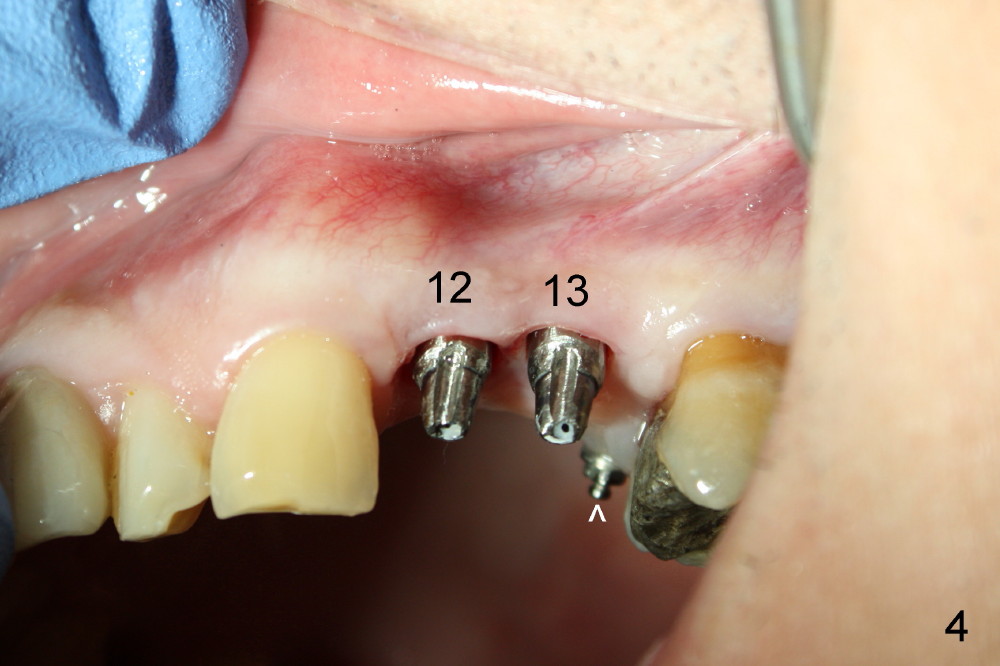

A 51-year-old man needs implants at the sites of #12,13,19 (Fig.1). The teeth #12 and 13 are extracted. An implant is placed at #19 (Fig.2 <). After osteointegration, an abutment is placed (Fig.2 A). The opposing tooth, #14, is found supraerupted. Two mini-implants are placed at the mesiobuccal and distolingual areas of #14 (Fig.3 (mirror view) <) and a power chain (*) is placed for intrusion. In the next 8 months, these 2 mini-implants become loose. Two new mini-implants are placed in the mesiolingual and distobuccal regions (Fig.4 ^). The one in the distobuccal region is loose after a while (Fig.6,7 >). In brief, mini-implants are not efficient in intrusion. At this time, the implants at the sites of #12,13 apparently osteointegrate (3 months post placement) and abutments are placed (Fig.4). Provisional crowns are fabricated (Fig.5). Brackets are placed between #11 and 15 with the bracket at #14 placed more coronally than those of the neighboring teeth (Fig.6-8). Mesially there are two excellent anchorages (#12,13) as well as the mesiolingual mini-implant. The distal anchorage is #15. In the next 5.5 months, the tooth #14 is intruded (Fig.9,10), but the 2nd molar is mobile (not as strong as #14). A longer mini-implant is placed in the distobuccal corner (>, more apical than before (Fig.7)). The distobuccal mini-implant is found to be mobile in 3 weeks (Fig.11). It appears that there is enough clearance for restoration of #19 (Fig.12). Power chains are placed between the mesiolingual mini-implant and #14 buccal tube until the appointment for crown prep. In this way, the lingual cusps may ascend (Fig.13 red arrow), while the buccal ones may descend (black arrow). The occlusal clearance will be more favorable.